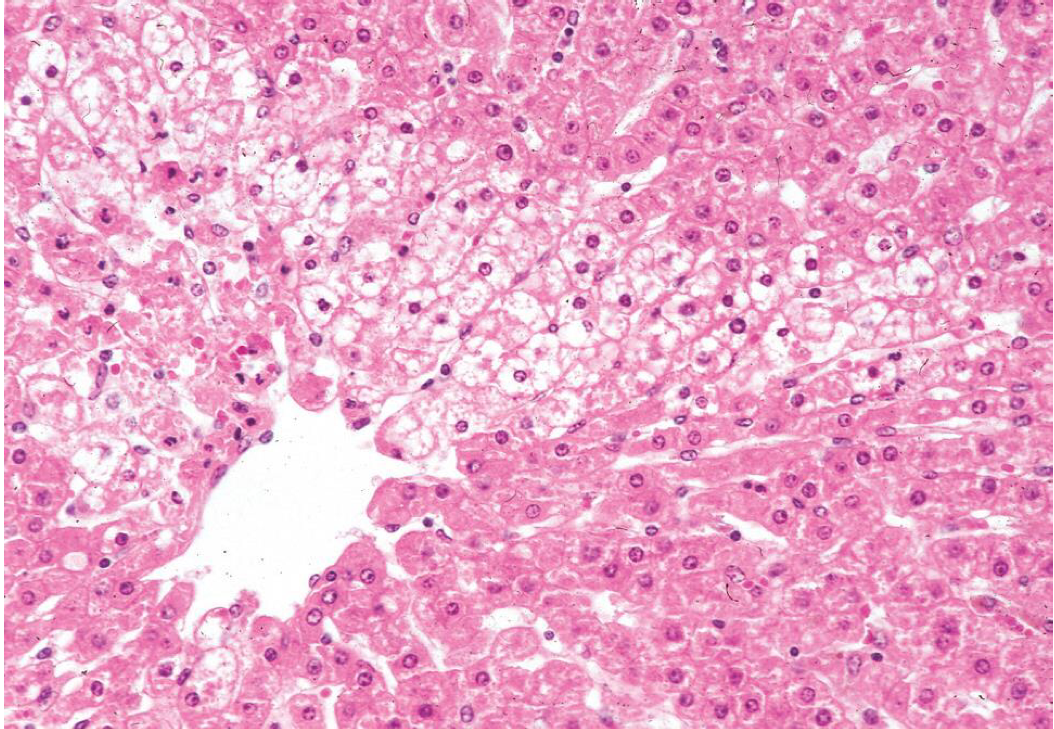

What are the mechanisms that would cause a liver to look like this?

This is hepatic lipidosis